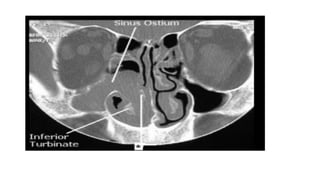

• Morphologically nasal polyps are oedematous

grape like protrusions most often originating

in the upper part of the nose around the

osteomeatal complex on the lateral wall.

• CT changes:

❍ mucosal changes within the osteomeatal complex